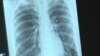

В Екатеринбурге официально объявлено об эпидемии ВИЧ. Свердловская область находится на первом месте в России по числу заболевших на сто тысяч населения. Инфицирован каждый пятидесятый житель Екатеринбурга. Часть заболевших находится в том числе и в колониях Свердловской области – там болен каждый пятый, 5 тысяч человек из 25 тысяч. Нужное лечение получают меньше половины из них, информирует Радио Свобода.

По официальной статистике, предоставленной пресс-службой ГУФСИН Свердловской области, только за январь и февраль 2019 года в лечебно-исправительных учреждениях умерли от всех причин 25 человек, из них по болезни – 24 человека. В том числе, от ВИЧ-инфекции умерло за два месяца 12 человек, то есть половина.

Основным источником информации для заключенного обычно становятся не врачи, а сокамерники, которые склонны недооценивать опасность заболевания и преувеличивать побочные эффекты от терапии. По статистике за 2018 год, всего 48% ВИЧ-инфицированных людей в колониях области получают нужное лечение.

В апреле 2016 года Анне сообщили, что Алексей, который тогда сидел в ИК-2, попал в больницу с высокой температурой, после чего его отправили в ЛИУ-51 (Лечебное исправительное учреждение 51 ФСИН России. – РС), где отбывают наказание и параллельно лечатся заключенные, больные туберкулезом и ВИЧ.

ЛИУ-51